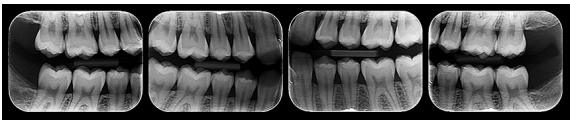

Analise os exames radiográficos a seguir:

De acordo com as imagens, podemos classificar estas radiografias como: